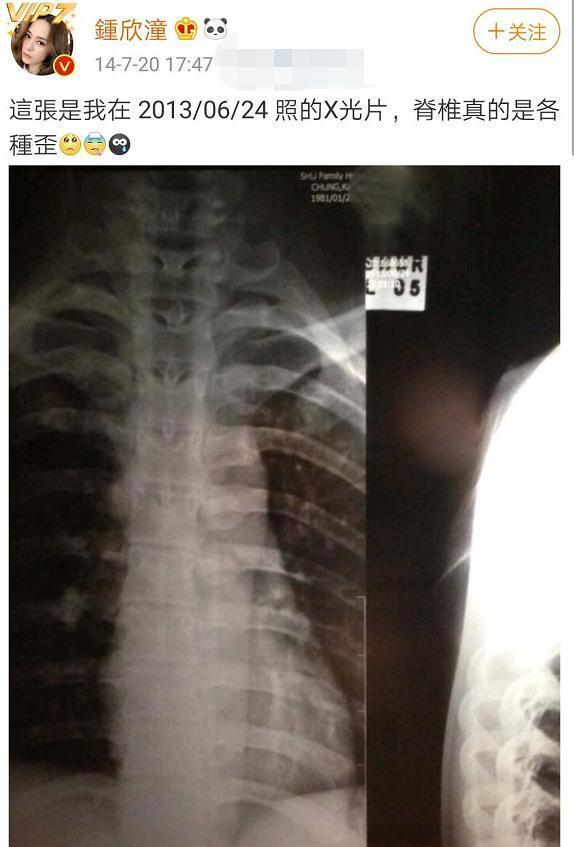

阿娇此前在接受采访时就说过:"之前脊柱歪了 , 很痛 , 痛了十个月 , 拍完剧要找医生把骨头拍正 , 之后又跌伤了尾骨 , 坐和站都很痛 , 要学空中瑜伽 。 "在受到网友的质疑后 , 她还曾晒出过自己的X光片 。